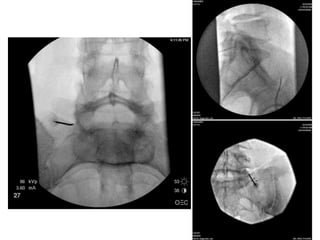

Tips & Tricks

Half way in advancing the electrode,

a critical point is encountered.

You should make a lateral x-ray

to make sure you are not advancing

over the ilium,

but indeed advancing into

the deep interosseous ligament

Lateral view

mainly to check if you are staying in contact with

the sacral posterium

Electrode is then advanced

Maintaining continuous contact with sacrum,

on a cephalad and slightly lateral line,

staying lateral to the sacral foramen,

medial to the sacroiliac joint, and

ventral to the ilium,

until contact with the sacral ala

prevents further advancement

AP view Endpoint

adjacent to the S1 posterolateral branches